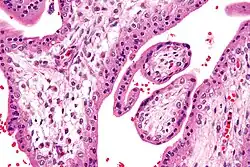

Chorionvilli (H&E-kleuring)

Chorionvilli zeer sterke vergroting. (H&E-kleuring)